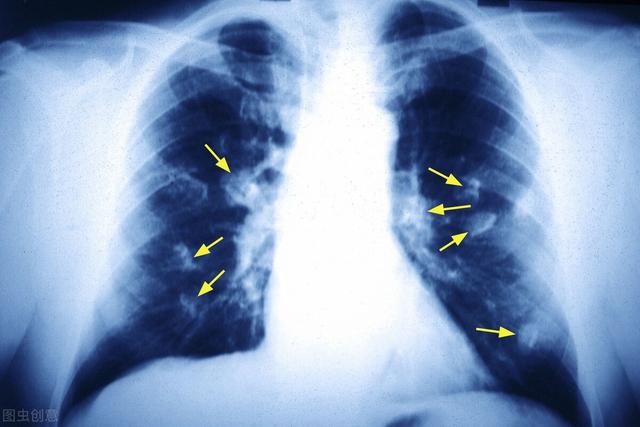

肺癌是我国最常见的恶性肿瘤之一,居癌症死亡率首位,及早发现,及早治疗,对肺癌的防治很重要。